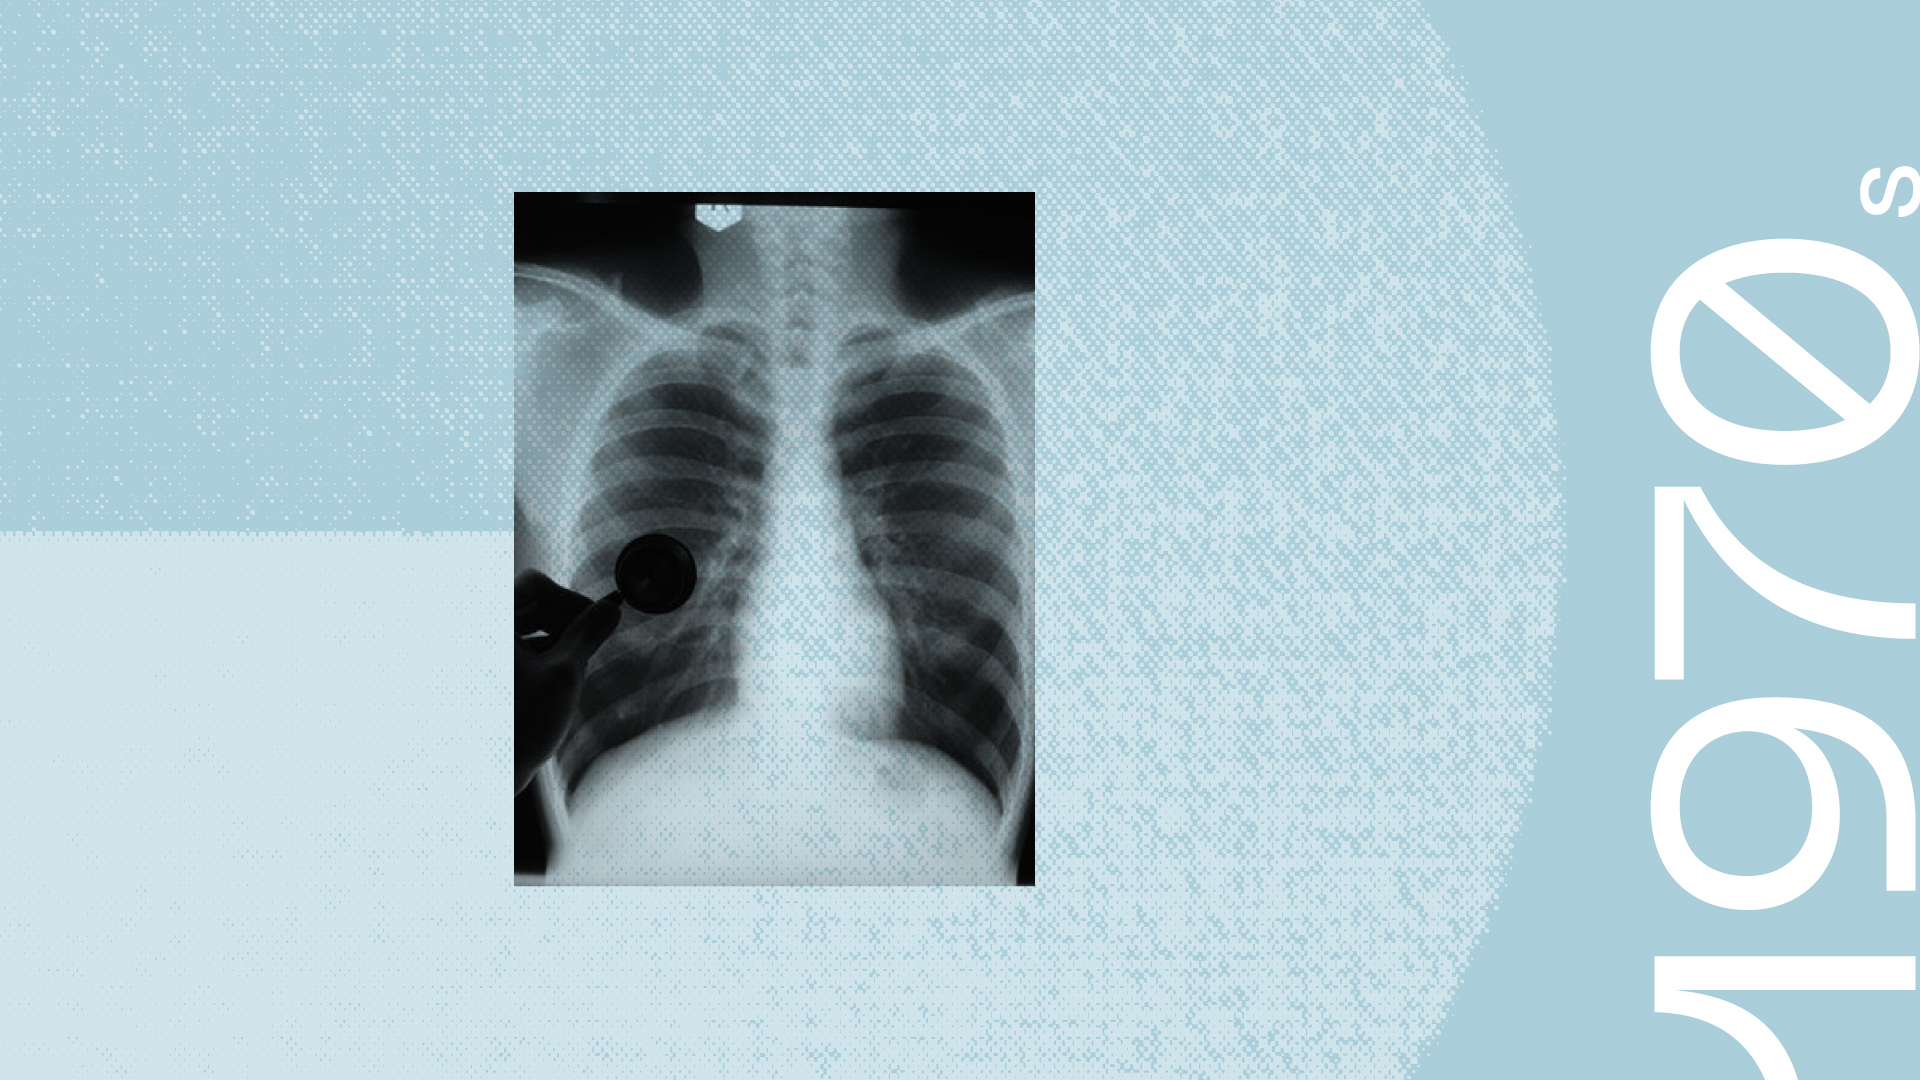

SRI researchers conducted a series of studies that modeled the pathogenesis of human respiratory diseases such as emphysema and chronic obstructive lung disease. The studies proved that these diseases were caused in humans by common contaminants of air derived from industrial and automobile exhausts and tobacco smoke. The results were fundamental to national and international efforts in setting allowable limits of nitrogen oxide and ozone contents in industrial exhausts and indoor air-quality standards.